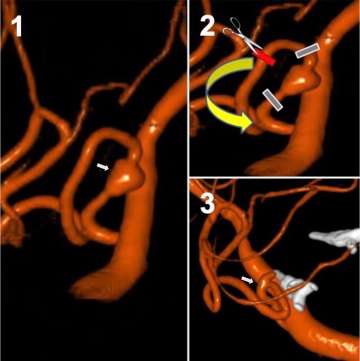

• Microsurgical clipping: In this technique, the neurosurgeon places a titanium clip across the neck/base of the aneurysm to cut off blood flow into the aneurysm, eliminate pressure on the aneurysm, and to prevent rupture.  This is technique with excellent long-term outcomes, and it has been continuously refined over the years since its first use in the 1930s (Figure 7).

• Aneurysm trapping and bypass: Open surgery is used to trap (block/exclude) the weak area of the vessel containing the aneurysm. A bypass is then performed to redirect blood flow around the trapped aneurysm, thereby keeping the vessel beyond the occlusion flowing, and preventing brain damage.  This technique has many nuances to it and is customized based on patient-specific anatomy and blood flow needs (Figure 8).

Illustration of dissecting Posterior Inferior Cerebellar Artery

Figure 8. Trap and bypass of a ruptured dissecting Posterior Inferior Cerebellar Artery (PICA) aneurysm - Panel 1 is a 3D angiogram lateral view of the dissecting aneurysm (arrow) dilating the PICA.